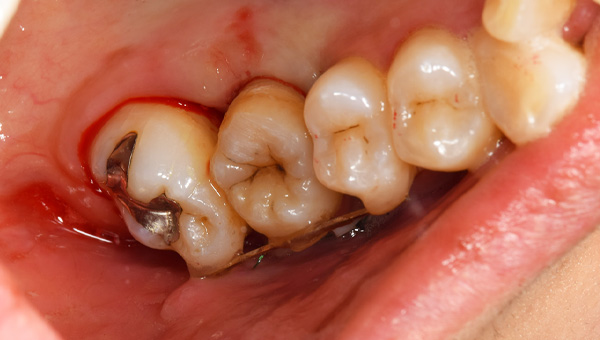

初診時の口腔内

説明:

初診時の口腔内です。かぶせ物があり、一見虫歯とはわからないです。